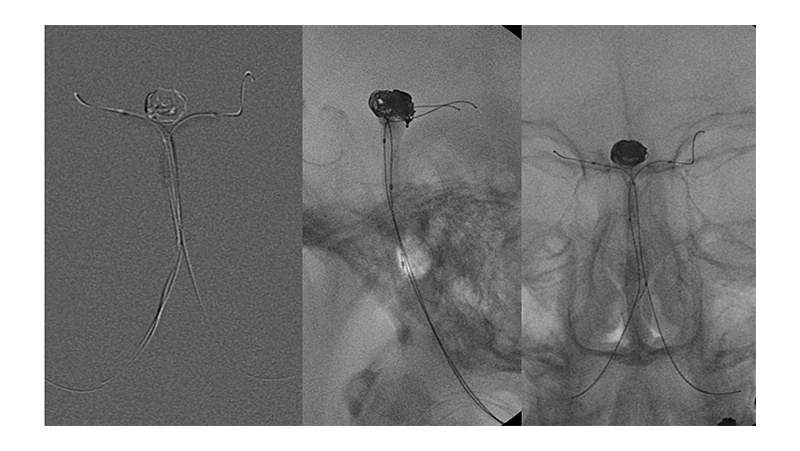

Εικόνα 4: Τοποθέτηση δύο μπαλονιών μπροστά στον αυχένα του ανευρύσματος, από το ανώτερο τριτημόριο της βασικής, στο Ρ1 των οπισθίων εγκεφαλικών αρτηριών εκατέρωθεν. Ο μικροκαθετήρας γιά τον εμβολισμό έχει τοποθετηθεί μέσα στον σάκκο του ανευρύσματος (δεξιά εικόνα).

Εικόνα 5: Με φουσκωμένα τα δύο μπαλόνια γίνεται η τοποθέτηση των μεταλλικών σπειραμάτων και η πλήρωση του ανευρύσματος. Η πρόπτωση των coils προς το θυγατρικό αγγείο αποτρέπεται από την παρουσία των μπαλονιών προστασίας.